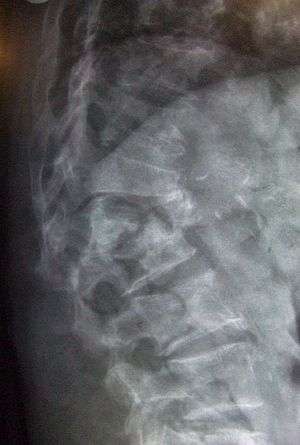

Elderly woman with osteoporosis showing a curved back from compression fractures of her back bones. | |

The main radiographic features of generalized osteoporosis are cortical thinning and increased radiolucency. Frequent complications of osteoporosis are vertebral fractures for which spinal radiography can help considerably in diagnosis and follow-up. Vertebral height measurements can objectively be made using plain-film X-rays by using several methods such as height loss together with area reduction, particularly when looking at vertical deformity in T4-L4, or by determining a spinal fracture index that takes into account the number of vertebrae involved. Involvement of multiple vertebral bodies leads to kyphosis of the thoracic spine, leading to what is known as dowager's hump.